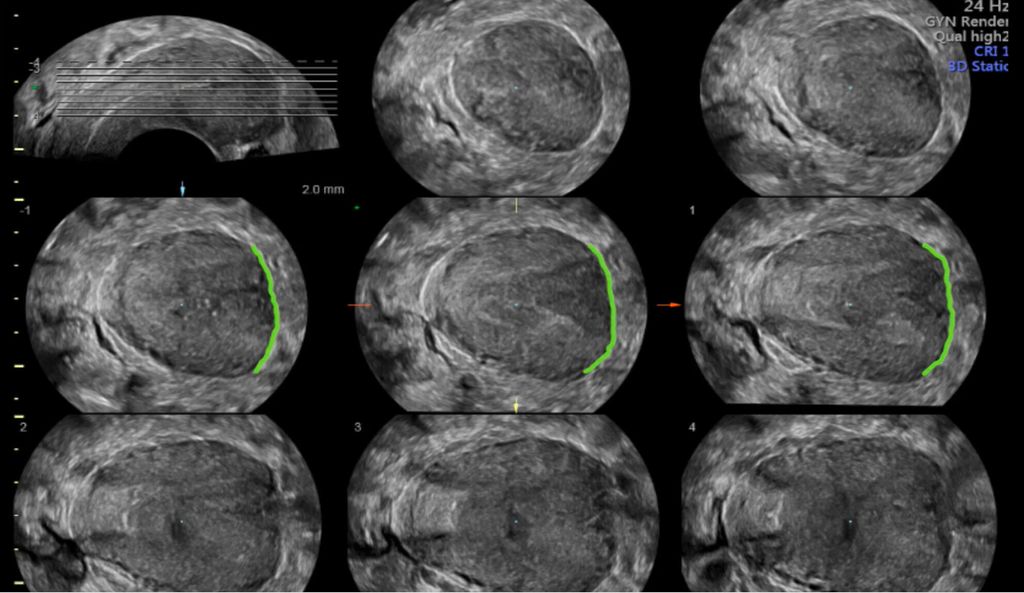

Ein weiterer Modus, «tomographic ultrasound imaging» (TUI) oder «multi-view», erlaubt die Darstellung mehrerer paralleler Schichten (bzw. multiplanarer Rekonstruktionen) in einem Raster. Dies ermöglicht, zusätzliche Details in bestimmen Bildabschnitten zu erhalten.

In unklaren Fällen, in denen die äussere Uteruskontur in der MPR nicht eindeutig zu sehen ist und so die Unterscheidung zwischen einem Uterus (sub-)septus und einem Uterus bicornis schwierig ist, hilft TUI bei der Differenzialdiagnose (Abb. 5 und 6).

Abb. 5: «Tomographic ultrasound imaging» (TUI). In mehreren parallelen Ebenen kann die äussere Uteruskontur analysiert werden (konvex vs. konkav)

Abb. 6: Uterus bicornis. Ist die äussere Uteruskontur in der MPR nicht eindeutig zu erkennen, hilft TUI (rechts)